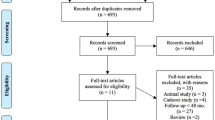

A search of three major databases yielded a total of 297 studies (77 in Pubmed, 106 in Embase, and 144 in Web of Science). The exclusion process was conducted using Endnote20 software to remove 140 duplicate studies. Two investigators independently screened the remaining 157 articles by reviewing titles and abstracts, resulting in the exclusion of 103 irrelevant studies. Subsequently, the remaining 54 articles were assessed for full-text availability. Among them, five studies could not be obtained for full text, while another 28 studies were excluded based on the predefined inclusion and exclusion criteria. Additionally, four studies were identified as duplicates and two were not written in English. Finally, a total of fifteen eligible studies were included in the meta-analysis. The screening flow chart is in Fig. 1.